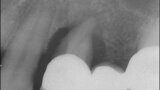

Buccal root of the bifurcated maxillary premolar—a danger zone during root canal therapy